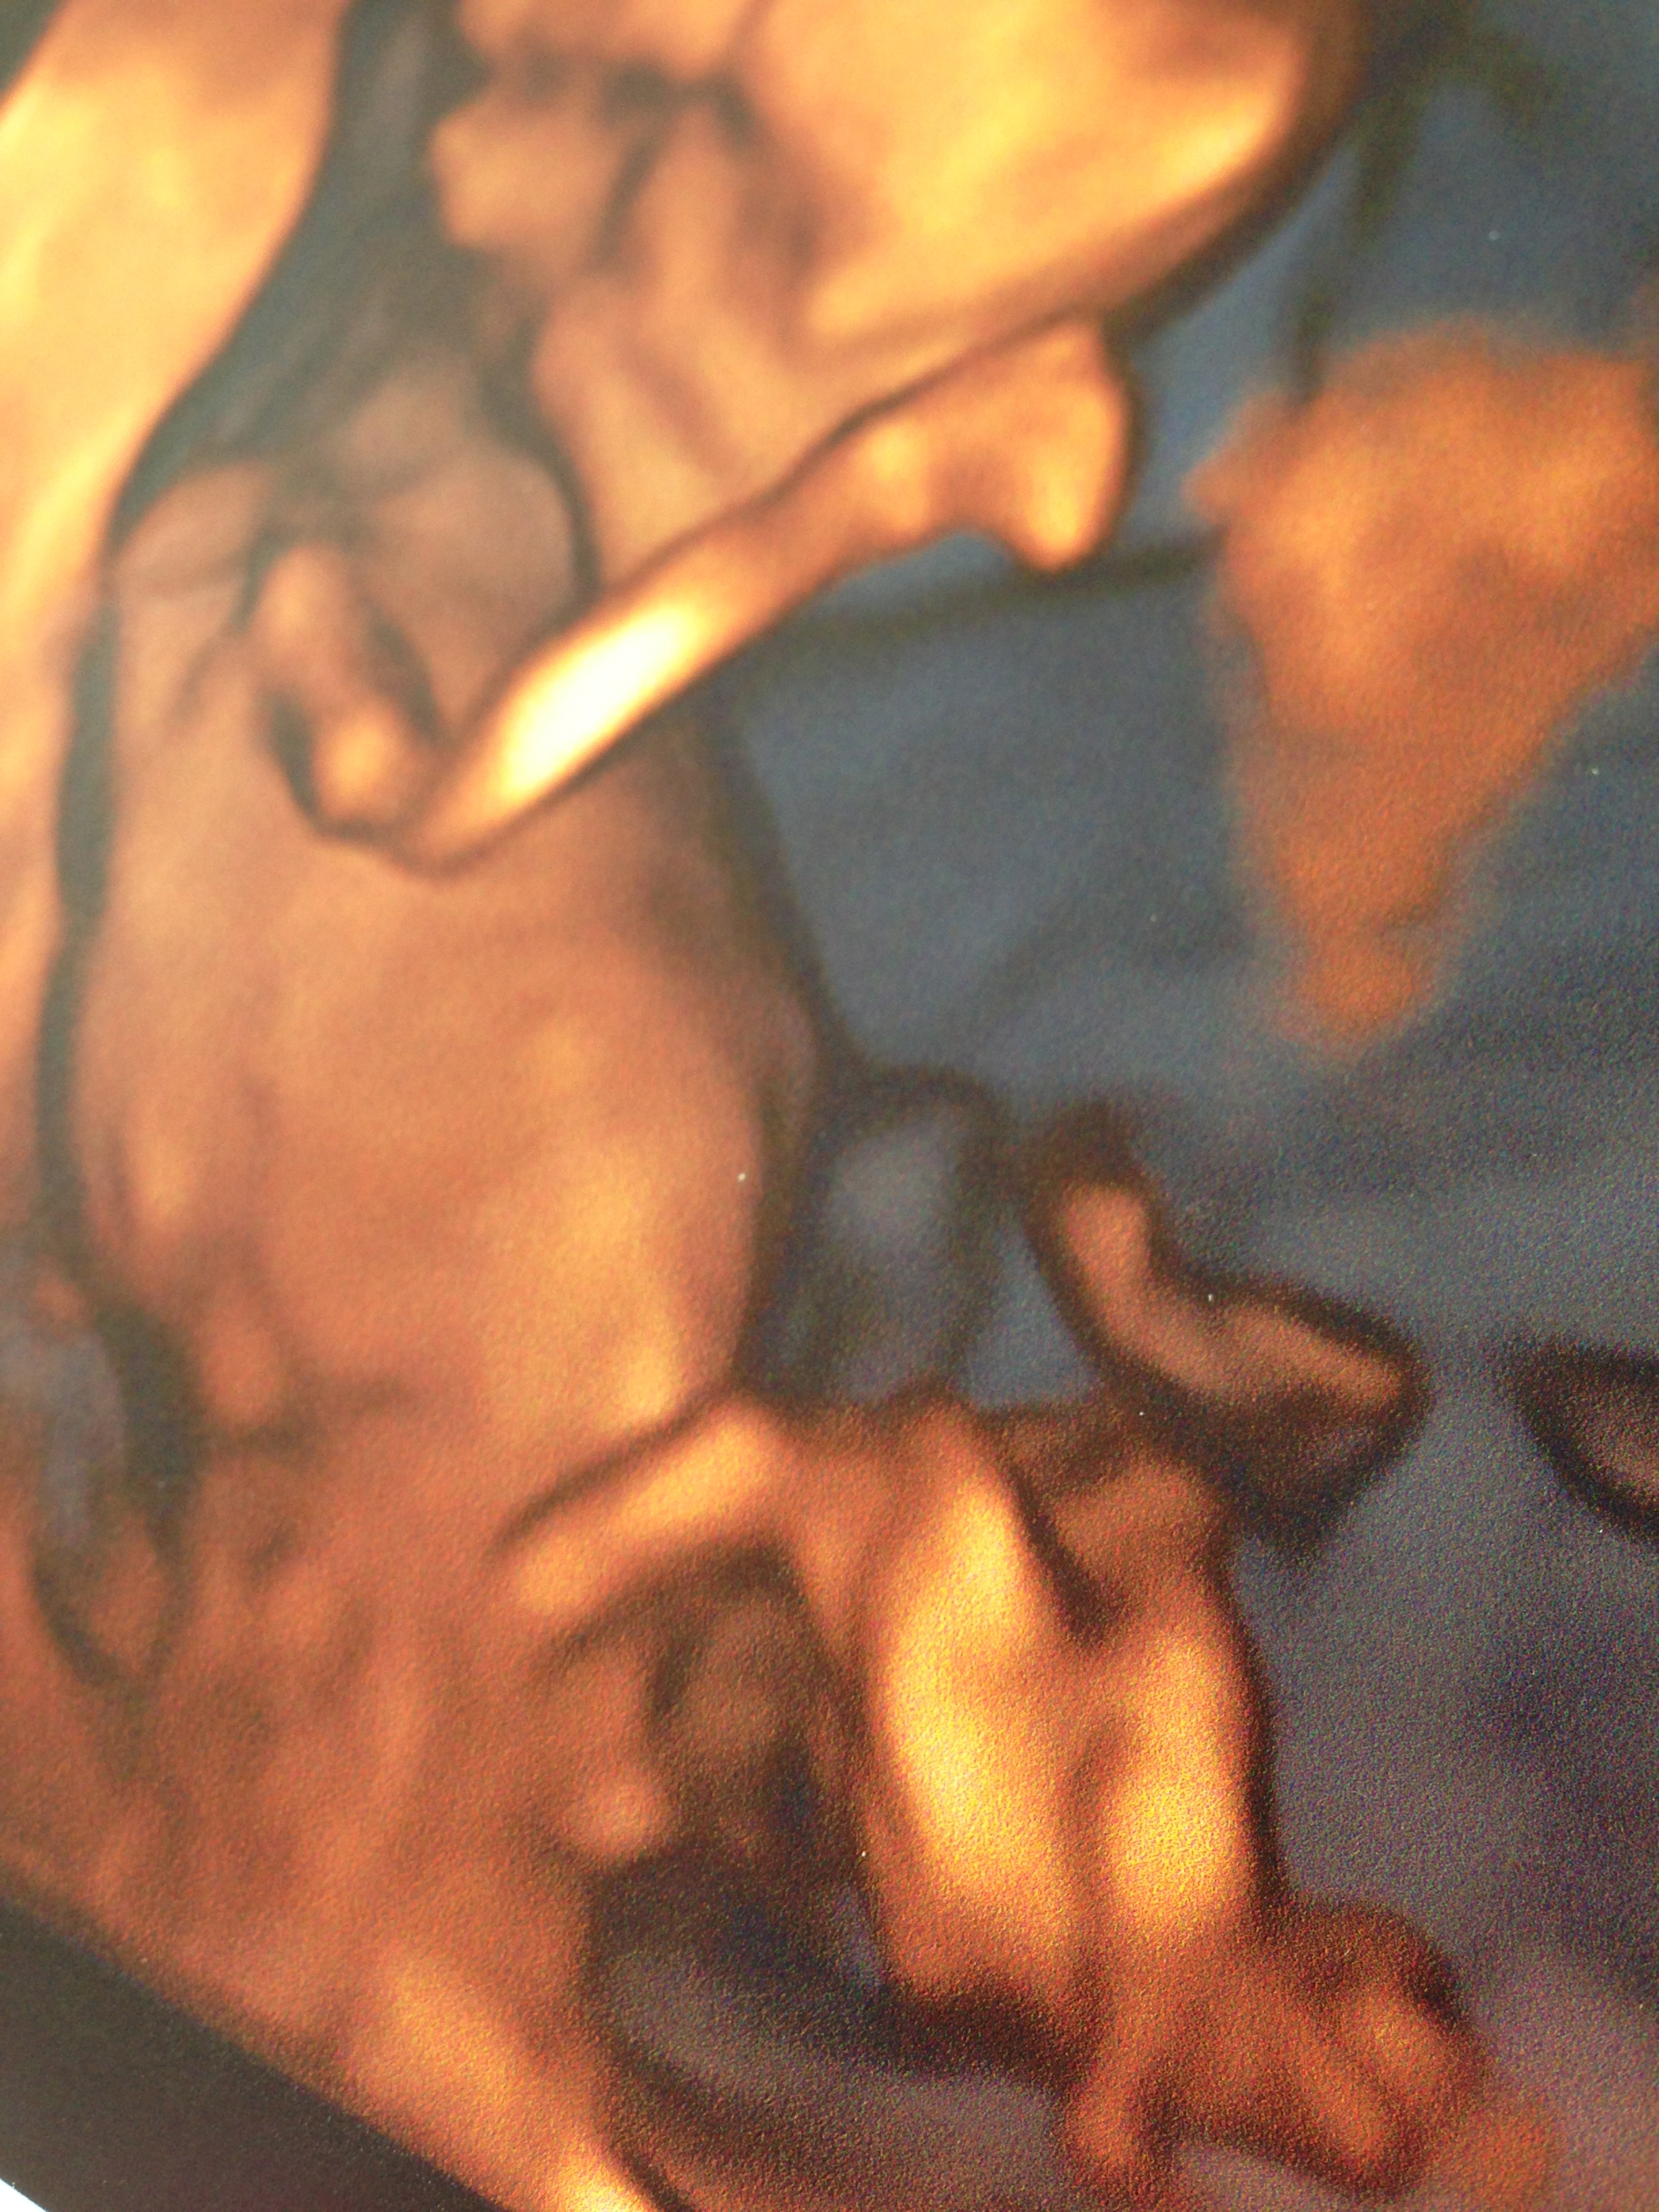

Another pictureAttachment 16729

I think girl on second pic (lower upload).

If that is the nub (on the newer pic), I think girl since it is long and pointed downwards.